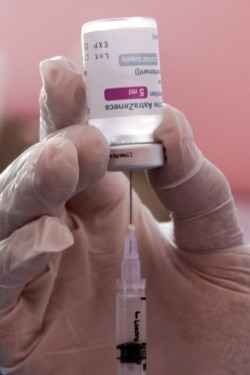

Juru bicara Vaksinasi COVID-19 Kementerian Kesehatan (Kemenkes) Siti Nadia Tarmidzi mengungkapkan kejadian ikutan pasca imunisasi (KIPI) yang ditemukan pasca penyuntikan vaksin AstraZeneca masih termasuk ringan.

Untuk itu, pemerintah akan melanjutkan program vaksinasi COVID-19 dengan AstraZeneca karena vaksin tersebut dinilai lebih besar manfaatnya daripada risikonya.

“Tidak ditemukan adanya KIPI yang berat pasca penyuntikan vaksin AstraZeneca ataupun keluhan yang kita ketahui,” ungkap Nadia dalam telekonferensi pers, di Jakarta, Selasa (30/3).

Berdasarkan laporan yang diterimanya, kata Nadia, efek samping penyuntikan vaksin AstraZeneca hanya terjadi pada 1-10 persen penerima vaksin. Keluhan yang disampaikan antara lain demam di atas 38 derajat celcius, bengkak, serta adanya rasa sakit pada tempat suntikan.

“Sekali lagi kami ingin sampaikan bahwa vaksin ini lebih besar manfaatnya dibandingkan dengan risikonya,” tegasnya.

Nadia melanjutkan, 1,1 juta dosis vaksin AstraZeneca yang didapatkan pemerintah Indonesia lewat fasilitas COVAX saat ini telah didistribusikan ke tujuh provinsi, yakni Bali, Jawa Timur, Nusa Tenggara, Kepulauan Riau, Sulawesi Utara, Maluku, dan DKI Jakarta.

Pada kesempatan yang sama Ketua Komisi Nasional (Komnas) KIPI, Hendra Irawan Satari, mengungkapkan pihaknya telah menerima laporan dari Komisi Daerah (Komda) KIPI di Sulawesi Utara yang mengalami KIPI, seperti menggigil, demam dan pegal pasca disuntik vaksin AstraZeneca.

Akibat keluhan tersebut, Kepala Dinas Kesehatan Sulawesi Utara menghentikan sementara pemberian vaksin itu. Namun, setelah dilakukan investigasi, observasi dan berdasarkan data yang ada diketahui bahwa empat orang yang mengalami KIPI tersebut termasuk ringan.

Selain itu, kata Hendra, KIPI yang terjadi dalam kasus ini diakibatkan oleh kecemasan. Menurutnya, KIPI tidak selalu berkaitan dengan kandungan vaksin, tetapi bisa juga berkaitan dengan kecemasan.

Hendra mengatakan hampir semua penerima vaksin yang mengalami KIPI sudah sembuh saat pihaknya melakukan audit.

“Kemudian kami melaporkan ke Bapak Menkes dan Wamenkes karena kami mengeluarkan rekomendasi bahwa KIPI yang terjadi di Sulawesi Utara bersifat ringan dan sebagian kecil berkaitan dengan reaksi kecemasan sehingga kami keluarkan rekomendasi bahwa vaksin ini dapat diteruskan dalam Program Imunisasi Nasional di Sulawesi Utara,” ungkap Hendra.

Vaksin AstraZeneca Aman

Ketua Indonesian Technical Advisory Group on Immunizattion (ITAGI), Sri Rezeki Hadinegoro, memastikan bahwa vaksin COVID-19 buatan AstraZeneca aman untuk digunakan.

Menurutnya, kejadian pembekuan darah di beberapa negara di Eropa pasca disuntik AstraZeneca diyakini bukan diakibatkan oleh vaksin tersebut. Meski demikian, ia menegaskan tetap perlunya pengawasan yang lebih ketat dalam penyuntikan vaksin AstraZeneca.

“Bahwa gangguan pembekuan darah sebetulnya secara alami cukup tinggi, dan dengan adanya vaksinasi tidak menambah. Kalau dia disebabkan oleh vaksin pasti angka kejadiannya akan naik, ini tidak terjadi, kemudian bagaimana pun juga kita harus pantau hal ini, kita harus berhati-hati memantau secara serius, berkala. Ini yang kita anjurkan untuk dikerjakan pada Kemenkes,” ujar Sri.

Keamanan vaksin buatan Inggris ini, kata Sri, juga dilihat dari uji klinis yang dilakukan kepada lebih dari 20 ribu sukarelawan yang dikerjakan di Inggris, Afrika Selatan, dan Brazil. Di dalam uji klinis tersebut efek samping yang ditemukan pun bersifat ringan, dan tidak ada yang masuk rumah sakit, apalagi meninggal akibat vaksin AstraZeneca tersebut.

“Vaksin ini bisa diberikan di atas 18 tahun malah juga untuk lansia (lanjut usia -red). Untuk lansia sangat baik, aman, dan juga imunogenitasnya cukup tinggi. Tetap dua kali diberikan, vaksin pertama, vaksin kedua dengan interval dikatakan oleh WHO 4-8 minggu,” katanya.

Namun, tambahnya, ITAGI menyarankan sebaiknya interval pemberian vaksin berjarak delapan minggu. “Mungkin itu lebih baik karena melihat efek sampingnya lebih rendah dan imunogenitasnya lebih baik,” paparnya.